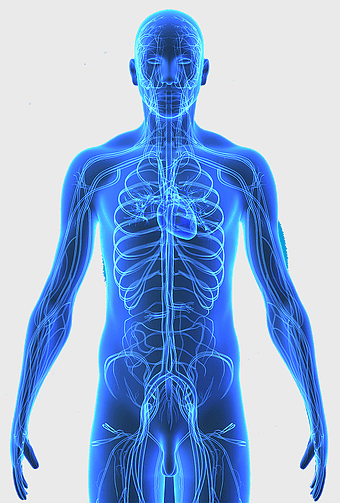

blue human anatomy illustration, human circulatory system diagram, digital human skeleton image, electric blue medical figure, human nervous system visualization, human body organ map, human health care graphic -

1644x2654px

human anatomy illustration, family medicine clinic visuals, blood pressure monitoring, shoulder and hip anatomy, medical diagram of human body, circulatory system depiction, health clinic -

723x1109px